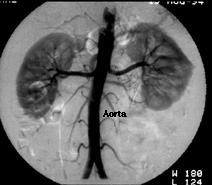

The top image shows an angiogram of the abdominal aorta. Iodinated contrast has been injected into a small catheter placed into the aorta through the femoral artery. The contrast flows into two kidneys. Each kidney is supplied by a single renal artery.